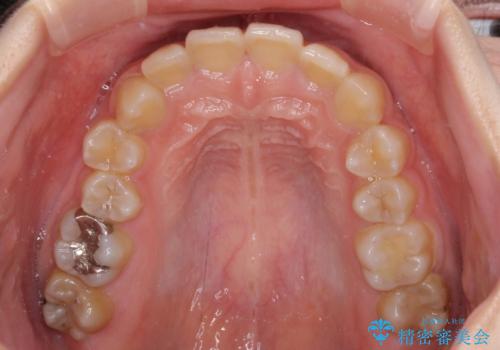

- 犬歯のクロスバイトを気にして来院された患者様です。

マウスピース矯正とワイヤー矯正の両方を提案しましたが、インビザラインの自己管理が煩わしいとのことで、ワイヤー装置による矯正治療を行うこととしました。

犬歯は歯根が太くて長いため、クロスバイトを改善するのは大変であることが多いですが、比較的スムーズに改善することができました。

インビザラインであったら、もっと期間はかかっていたような印象です。